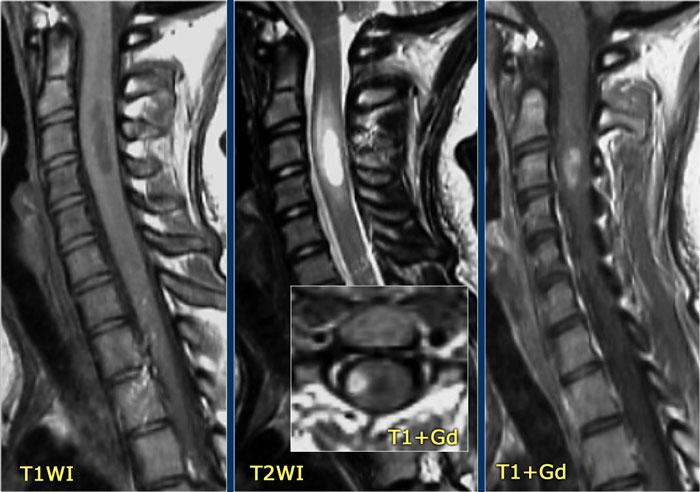

Hình ảnh bên trái của một trẻ vị thành niên với bệnh sử điển hình:

- Ba tuần sau nhiễm trùng đường hô hấp, khởi phát đột ngột các triệu chứng thần kinh.

-

Loạn vận ngôn, khó nuốt, liệt tứ chi.

Rối loạn vận nhãn và rối loạn ý thức.

Bệnh sử lâm sàng này điển hình cho ADEM.

Thông thường não cũng bị tổn thương.

30% trường hợp có tổn thương tủy sống.

Các đặc điểm hình ảnh trong trường hợp này cũng rất điển hình.

Có hình ảnh phù nề và tổn thương tủy tương tự như trong viêm tủy ngang (TM) và không có ngấm thuốc.

Tiếp tục xem các hình ảnh của não.

Trước tiên hãy quan sát các hình ảnh não và xác định điểm khác biệt so với tổn thương trong MS.

Những đặc điểm điển hình cho ADEM và ít gặp trong MS là:

- Tổn thương lan rộng vùng cầu não.

- Tổn thương hạch nền.

Hình ảnh MRI theo dõi cho thấy tủy sống đã trở về bình thường.